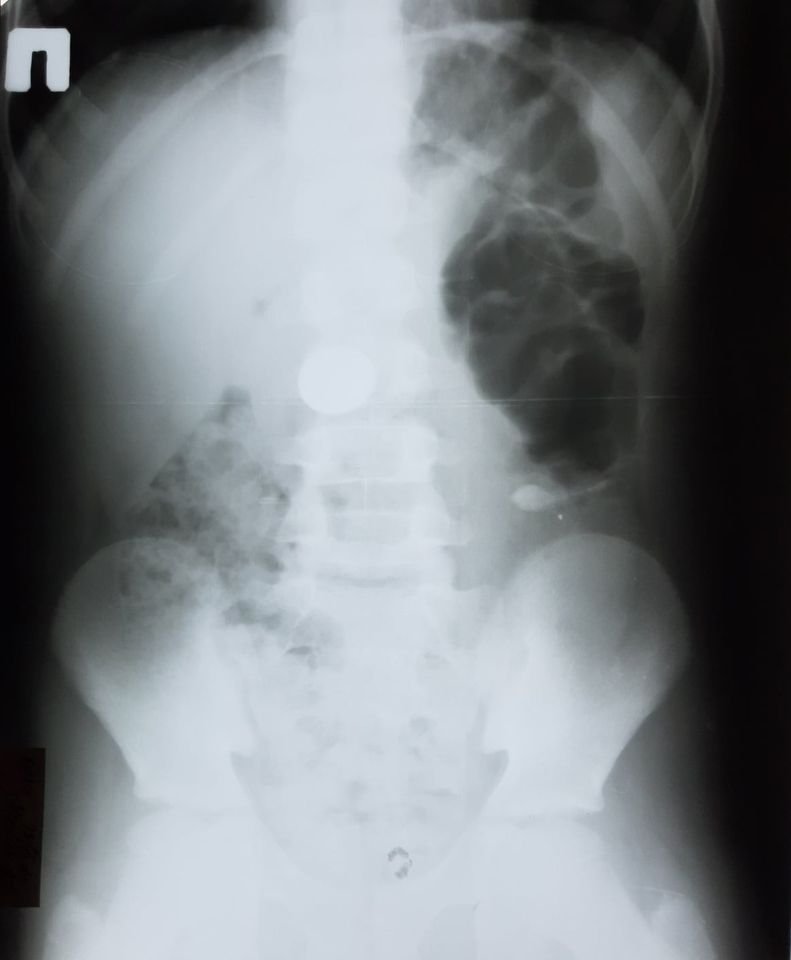

20 ноября в это же отделение попал 10-летний ребенок с монетой в желудке. Предмет также извлекли под седацией. Ребенок в безопасности.